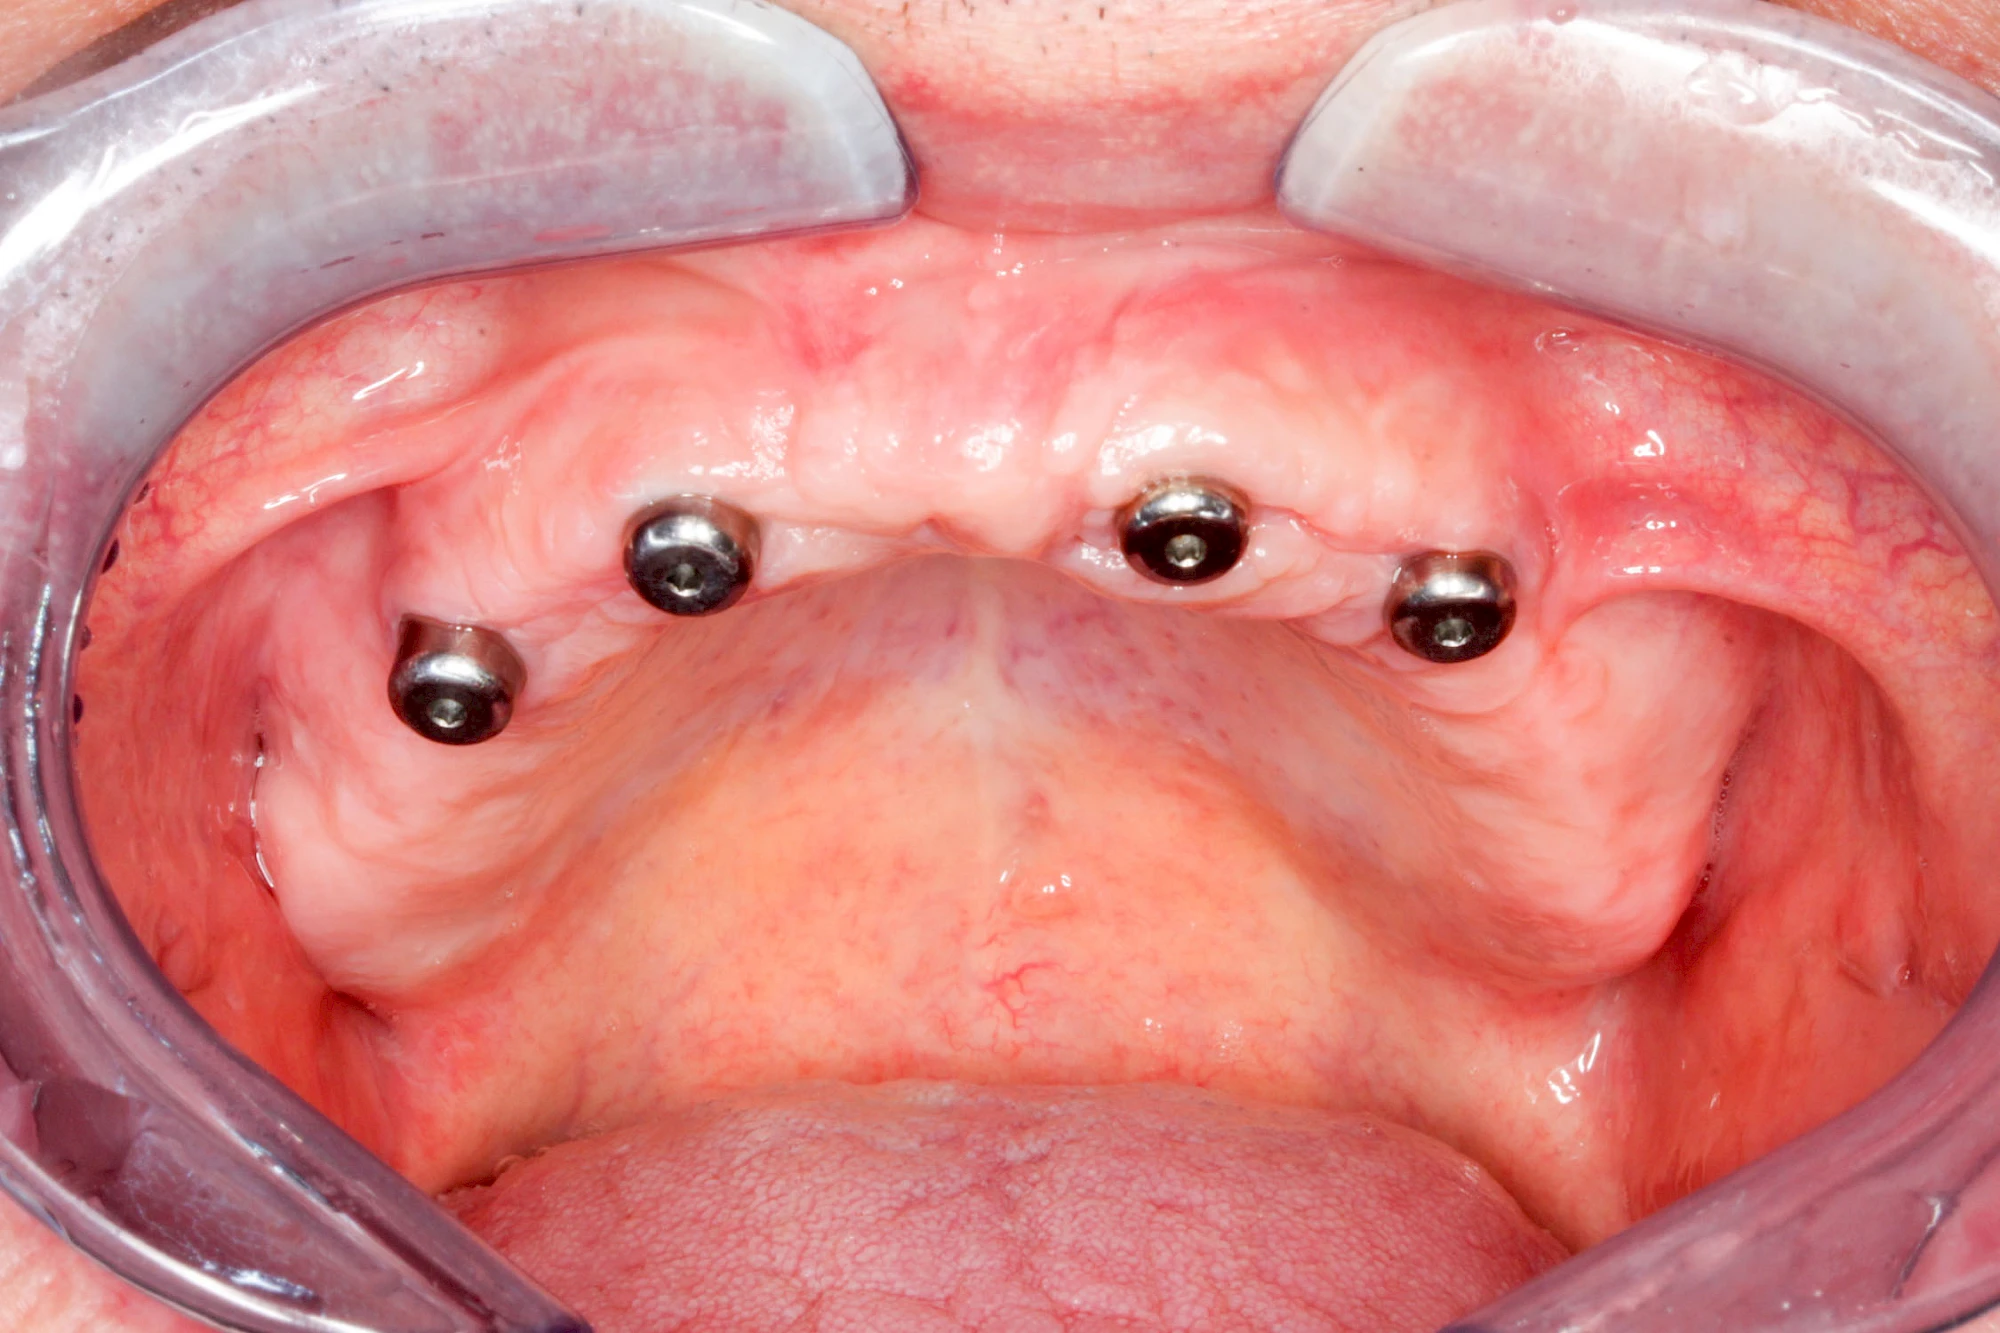

Bei herausnehmbaren Prothesen werden Implantate eingesetzt, um den Halt und den Tragekomfort der Prothesen zu verbessern. Dazu kommen verschiedene Verbindungselemente zum Einsatz:

- Teleskope

- Kugelköpfe

- Tellerförmige Lokatoren

- Stege

- Magnete (selten)

Neben rein implantat-getragenen zahnärztlichen Versorgungen werden bei herausnehmbaren Prothesen Implantate auch in Sinne einer "strategischen Pfeilervermehrung" ergänzend zu eigenen Zähnen zur Verankerung eines Zahnersatzes genutzt.

Varianten zur Verankerung von abnehmbarem Zahnersatz auf Implantaten